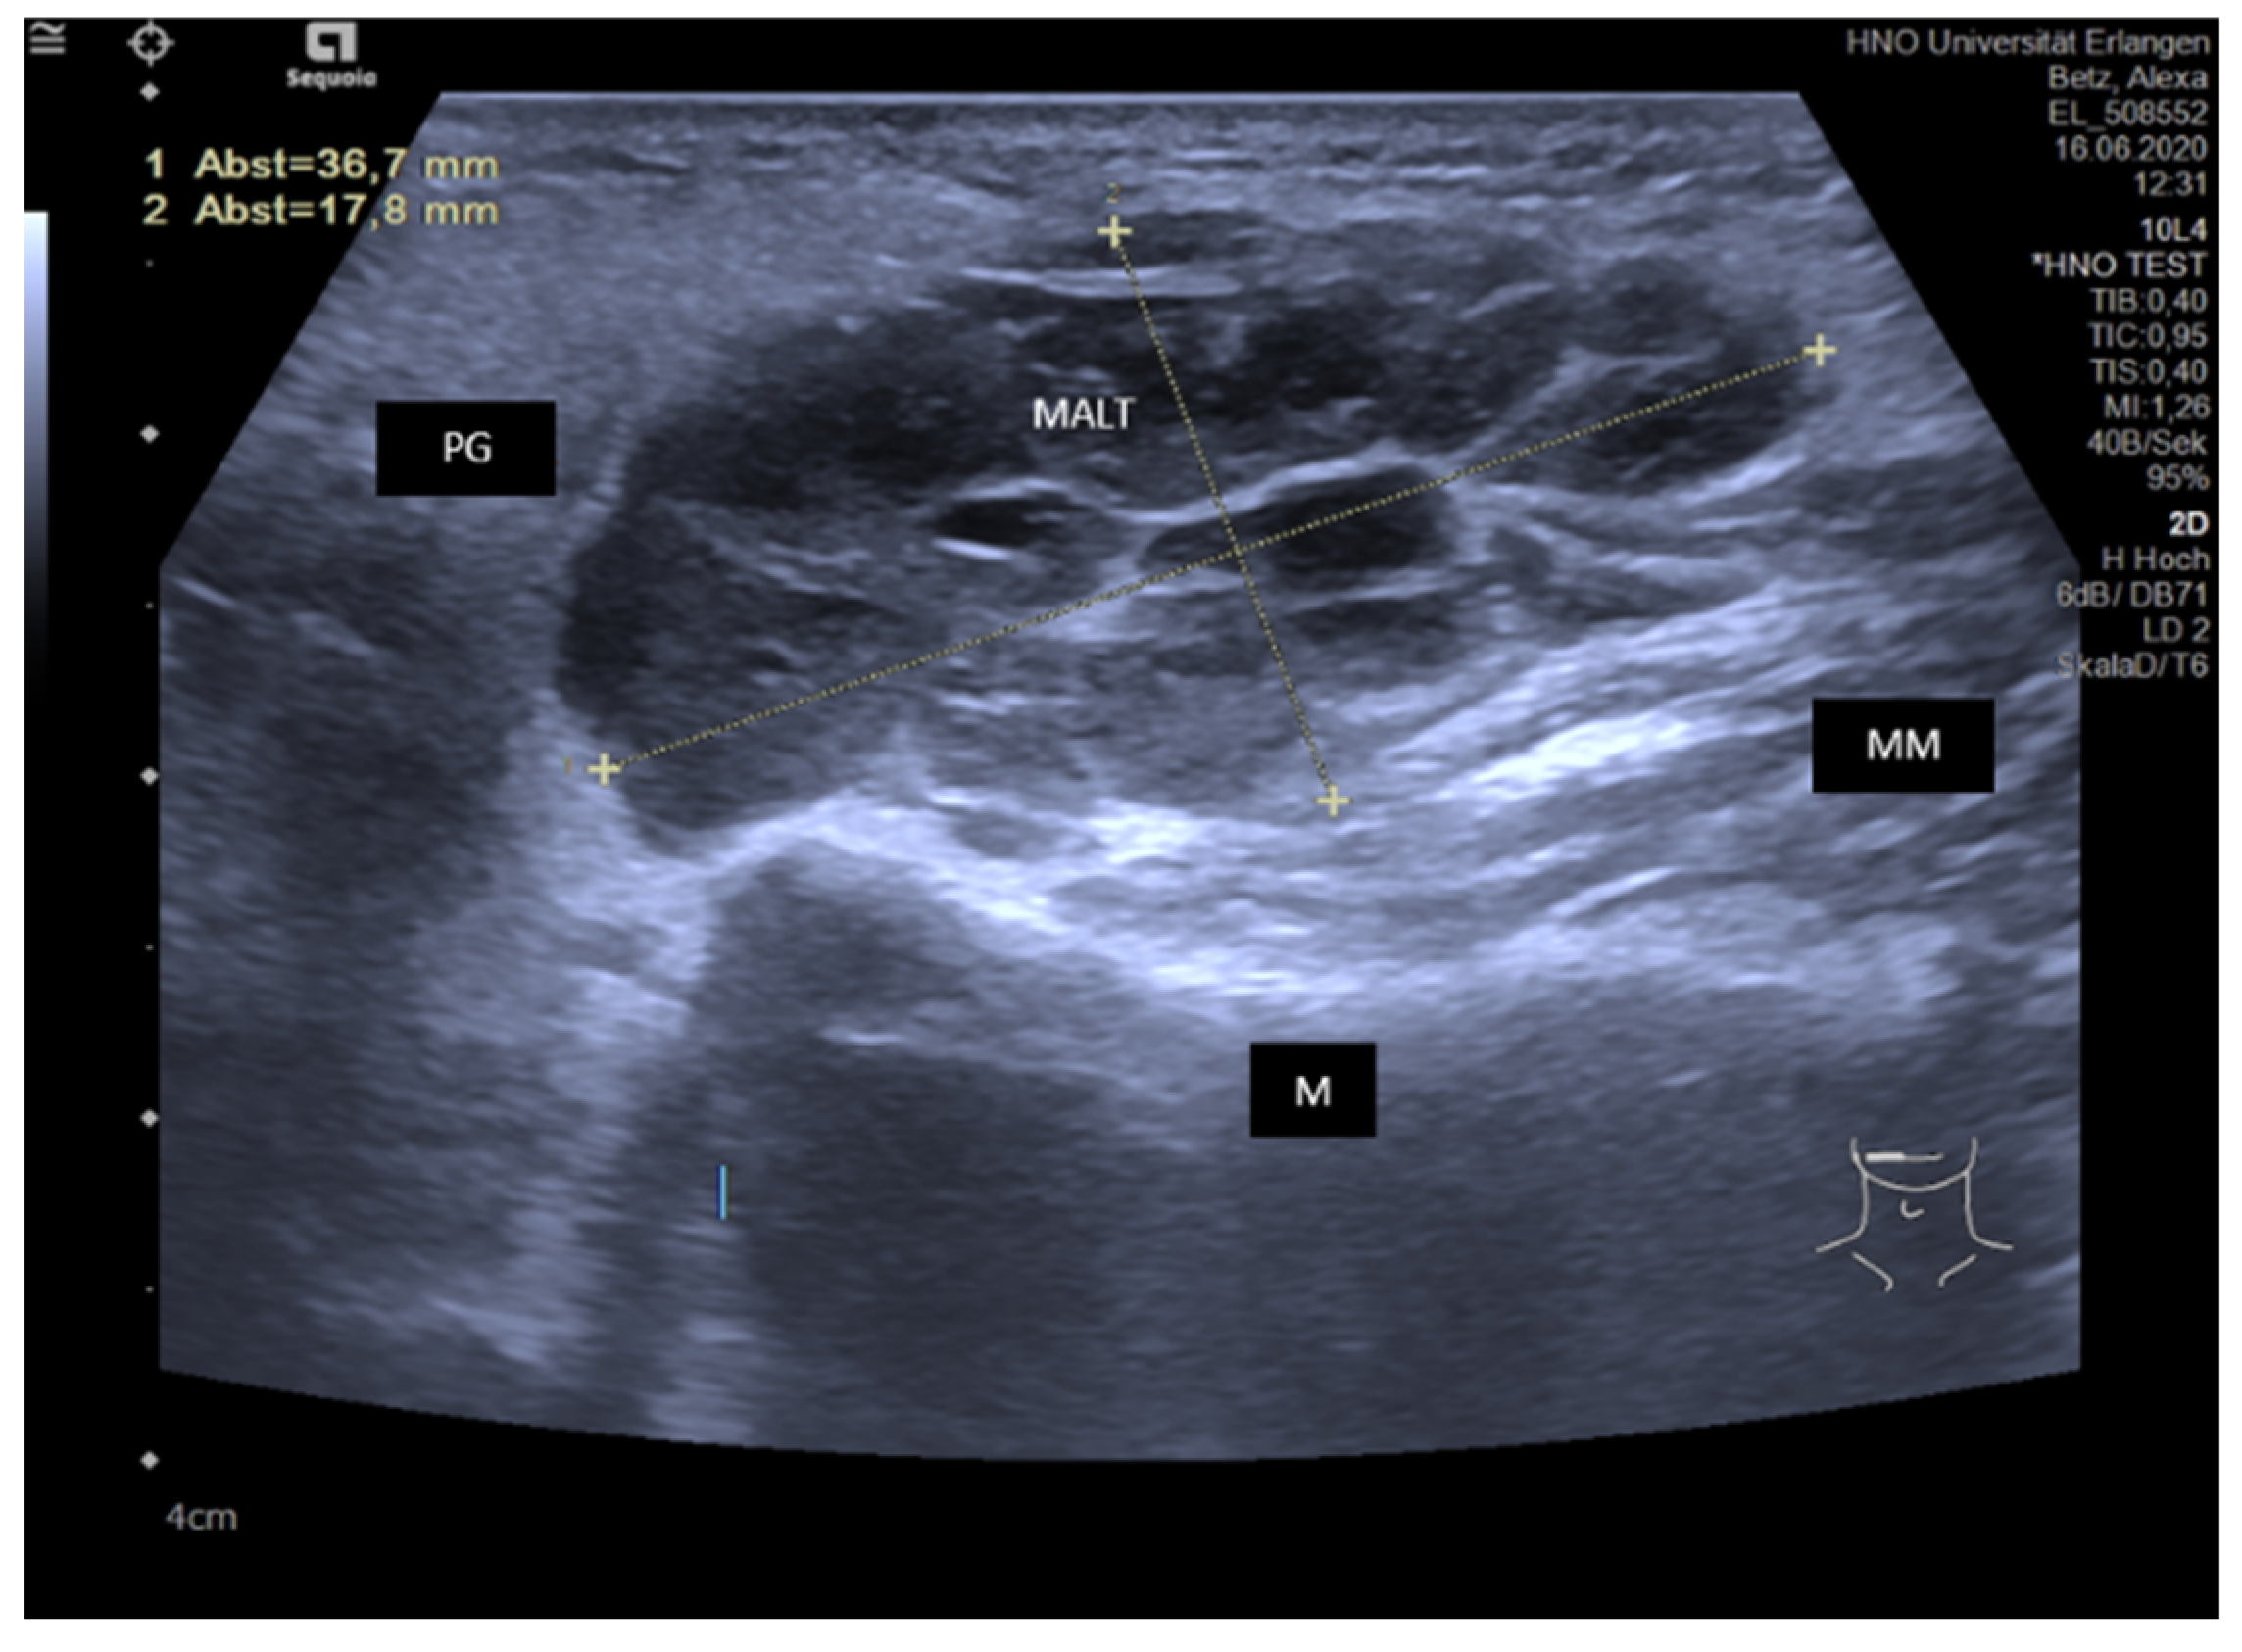

3.4. Disease-Associated Inflammatory Sialadenitis with Sialodochitis (and Possible Secondary Obstruction)

3.4.4. IgG4-Associated Involvement of Salivary Glands